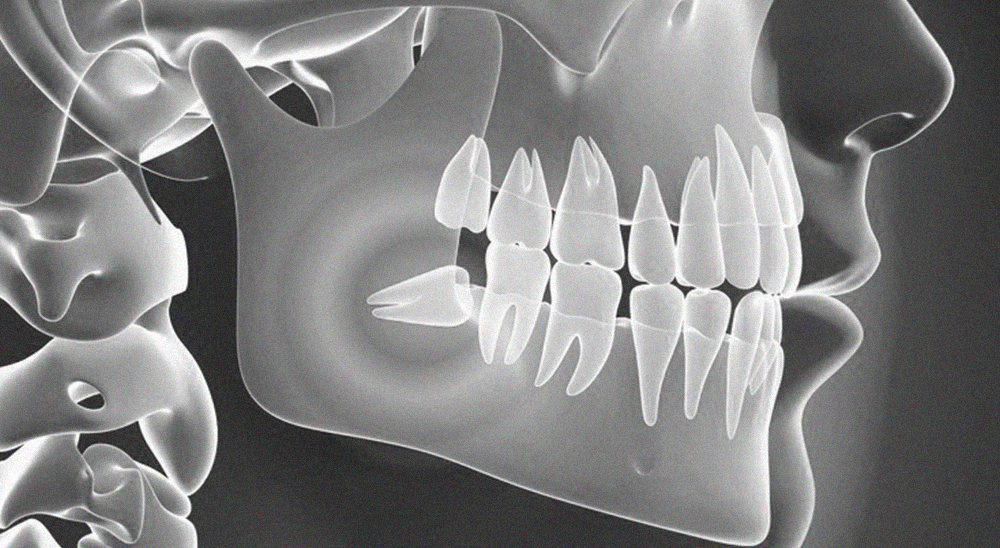

치아 건강,

신중한 진료가

더 오래 지켜줍니다

치료의 끝이 아닌, 치아보존의 시작을 만듭니다.

연세일등치과는 충치를 단순히 메우는 것보다

치아의 남은 구조를 얼마나 많이 보존할 수 있을지를

먼저 생각합니다.

이를 위해 치료 전 단계부터 정밀한 진단을 통해

건강한 부위와 손상된 부위를 구분하고,

치료 범위를 필요한 만큼만 설정합니다.

이러한 보존 중심 접근은 단순한 철학이 아니라,

연세일등치과의 진료 시스템 그 자체입니다.